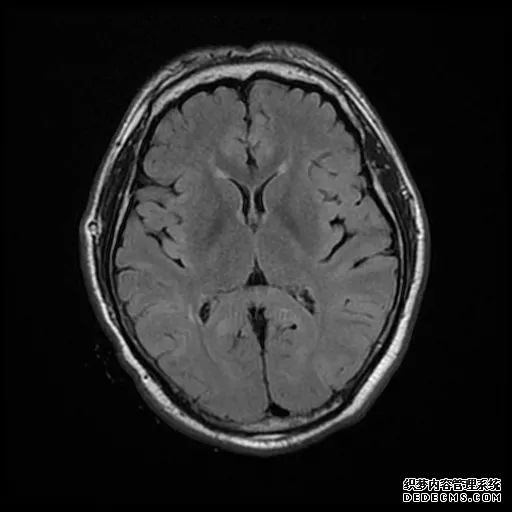

脑MRI显示尾状核、扁豆状核和脑梗头部T2/FLAIR呈双侧对称异常高信号。扩散限制涉及这些区域,其特征是扩散加权DWI(B-1000)上的高强度,ADC图上相应的减弱强度。

印象:通过将这些成像模式与临床和实验室检查结果相结合,就有可能得出低血糖性脑病。

影像影响内囊后肢、大脑皮层(特别是枕叶和岛叶)、海马和基底节区,常是双边对称性的。